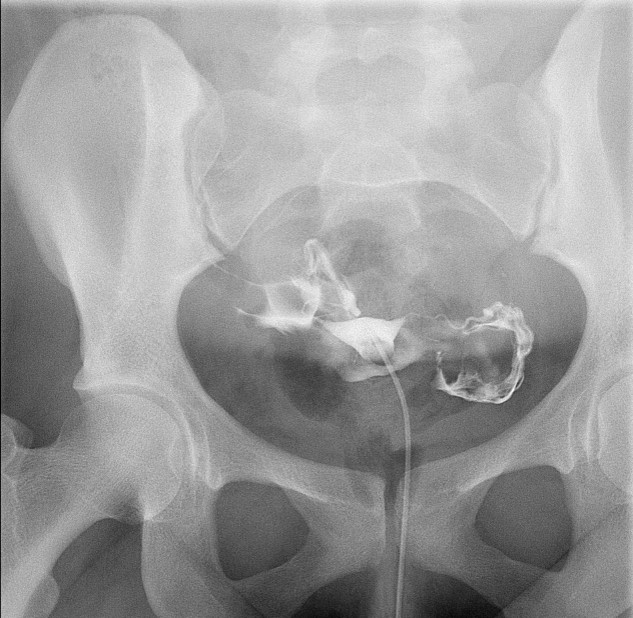

- When reviewing the preliminary scout film, you should see multiple surgical chain sutures in the pelvis

(key image 31)

(key image 32).